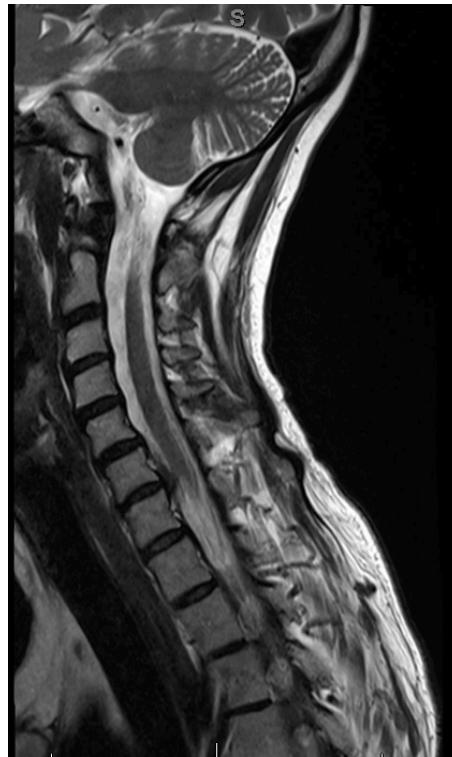

Imaging:

- MRI: Study of choice to evaluate degree of spinal cord and nerve root compression

Imaging Examples:

Surgical Treatment - Anterior Cervical Discectomy and Fusion: